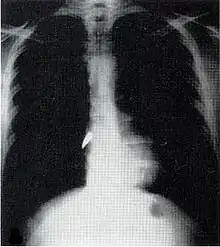

X-ray showing a bullet (white spot) in the heart

Most penetrating injuries are chest wounds and have a mortality rate (death rate) of under 10%.[14] Penetrating chest trauma can injure vital organs such as the heart and lungs and can interfere with breathing and circulation. Lung injuries that can be caused by penetrating trauma include pulmonary laceration (a cut or tear) pulmonary contusion (a bruise), hemothorax (an accumulation of blood in the chest cavity outside of the lung), pneumothorax (an accumulation of air in the chest cavity) and hemopneumothorax (accumulation of both blood and air). Sucking chest wounds and tension pneumothorax may result.

Penetrating trauma can also cause injuries to the heart and circulatory system. When the heart is punctured, it may bleed profusely into the chest cavity if the membrane around it (the pericardium) is significantly torn, or it may cause pericardial tamponade if the pericardium is not disrupted.[15] In pericardial tamponade, blood escapes from the heart but is trapped within the pericardium, so pressure builds up between the pericardium and the heart, compressing the latter and interfering with its pumping.[15] Fractures of the ribs commonly produce penetrating chest trauma when sharp bone ends pierce tissues.